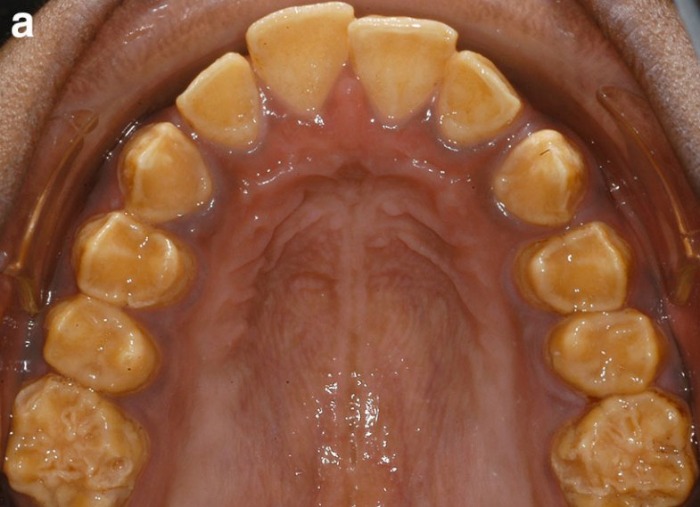

б) Визуализация:

1. Общая характеристика:

• Лучший диагностический критерий:

о Тонкая эмаль

о Одинаковая плотность эмали и дентина

• Морфология:

о Гипопластический тип:

- Тонкий периферический слой рентгеноконтрастной эмали

- Открытые контакты: свободное пространство между зубами:

Зубы выглядят «подготовленными к протезированию коронок» (процедура подготовки к установке протеза, при которой удаляется часть коронки)

- Часто обнаруживается резорбция непрорезавшихся зубов

о Агенезия эмали: отсутствие рентгеноконтрастной эмали, покрывающей дентин

о Гипоматурационный тип: плотность эмали равна плотности дентина

о Гипоминерализационный тип:

- Эмаль имеет такую же плотность, как и дентин

- Присутствуют непрорезавшиеся зубы

- Волнистый, неравномерный слой эмали на окклюзионных поверхностях

о Гипоматурационный/гипопластический тип:

- Тонкая, но рентгеноконтрастная эмаль или

- Эмаль нормальной толщины, но одинаковой плотности с дентином

- Иногда обнаруживается тауродонтизм

В норме эмаль имеет высокую рентгеноконтрастность по сравнению с дентином. При гипоматурационной форме НА эмаль и дентин имеют равную рентгеноконтрастность, а при гипоминерализованной форме — рентгеноконтрастность дентина выше. При гипопластической форме на рентгенограмме сразу виден тонкий слой эмали.